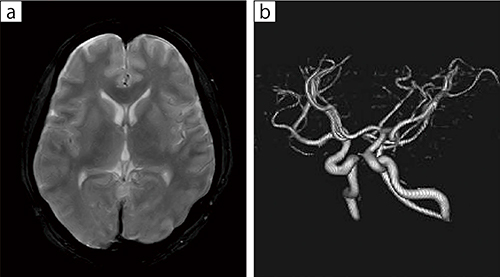

■症例3:脳ドック(閉所恐怖症あり)

40歳代,男性。脳ドックでも十分使用可能で,高磁場装置と変わらぬ画質が得られた。

a:T2*WI,TR/TE:1000/60,スライス厚:7mm,FOV:220mm,FA:90°,マトリックス512×512,撮像時間:4 : 50

b:MRA volume rendering,TR/TE:41.4/6.5,スライス厚:1.2mm,FOV:200mm,FA:90°,マトリックス220×116,撮像時間:9:36